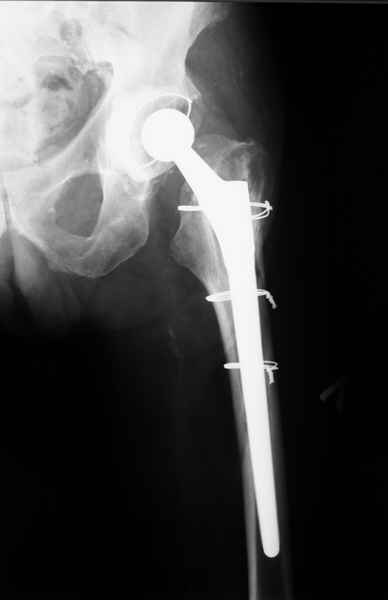

2. Применение ножки дистальной фиксации, мы отдаем предпочтение ножке Вагнера с фиксацией проксимального отдела на ножке. Более травматичное вмешательство, но при стабильной фиксации ножки реабилитация идет в обычном режиме.

Хочется показать два подобных случая, П-ка З. 72 лет и п-т Г. 80 лет. Сразу принимаю замечание, что это были ножки цементной фиксации, просто под руками не было бесцементника.

Пациента удалось осмотреть недавно. Достигнутый результат сохраняется. Перелом бедра сросся. Конечность опорная и безболезненная, ходит без трости. Ножка, похоже, реинтегрировалась, как и надеялись. Снимки и фото в приложении. Комментарии приветствуются.

Надо ли что-то делать дальше, как полагаете? Убрать винты? Убрать "удлинитель ножки"? Или оставить все, как есть? Спасибо заранее.